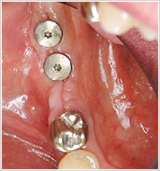

インプラントを埋入してから2週間後の写真です。 - 骨との結合

インプラントと骨の結合に、3ヶ月待ちました。

写真は、土台が入ったところです。

インプラントの土台のことを「アバットメント」と言います。 - 仮歯の装着